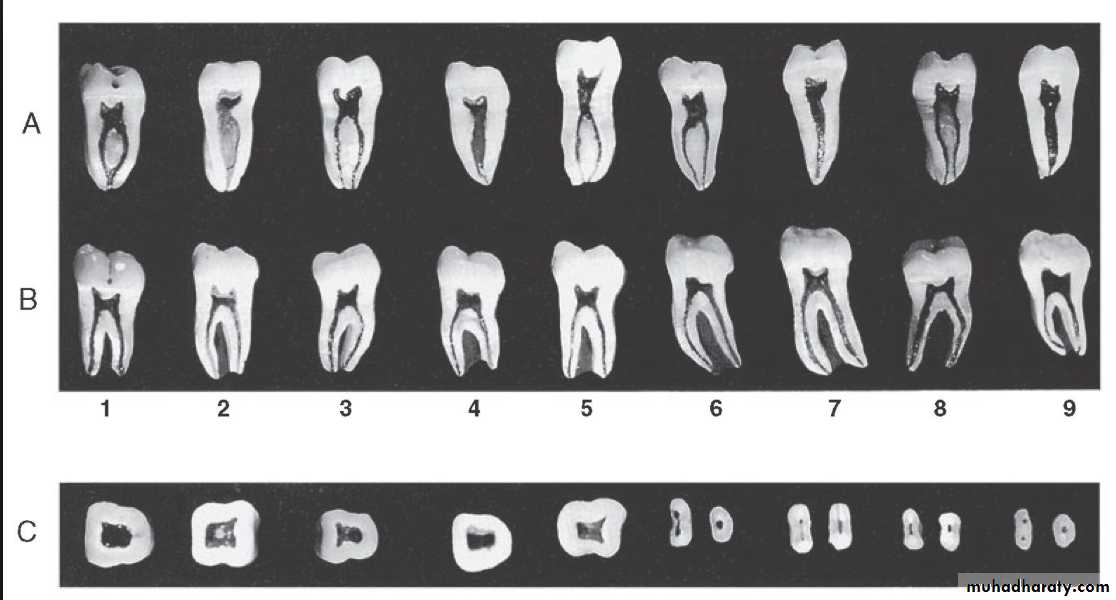

Pulp lies in the center of tooth and shapes itself to miniature form of tooth. This space is called pulp cavity which is divided into pulp chamber and root canalPulp Chamber

It reflects the external form of enamel at the time of eruption, but anatomy is less sharply defined.Root Canal

It is that portion of pulp preparation which extends from canal orifice to the apical foramen. The shape of root canal varies with size, shape, number of the roots in different teeth.The apical foramen is an aperture at or near the apex of a root through which nerves and blood vessels of the pulp enter or leave the pulp cavity.

Anatomy of Pulp

Pulp Chamber or coronal pulp, located in the crown of the tooth.

Root canal or radicular pulp, is the portion of the pulp located in the root area.

The apical foramen is the opening from the pulp at the apex of the tooth.Accessory canals or lateral canal, extra canal located on the lateral portions of the root.

Pulp horns